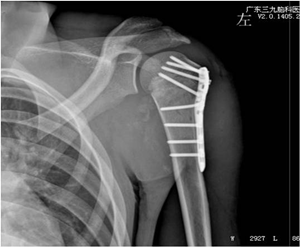

医院在予积极对症治疗的同时,请我科梁鹏医师诊治。在阿达的血压回升平稳后,由梁鹏医师主刀,为其进行左肱骨近端骨折切开复位内固定术。术后,阿达的骨折部位愈合良好,生命体征平稳。

▲术后 钢板内固定